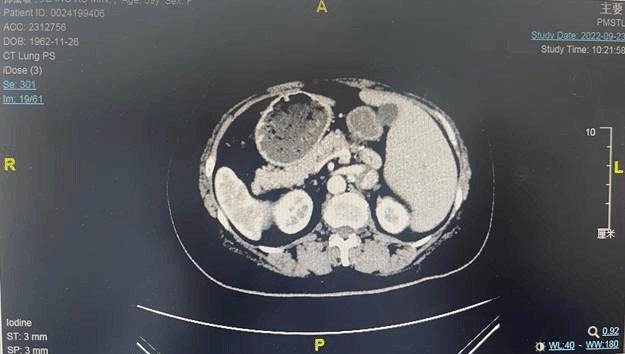

“按理说,人的肝脏都是长在右侧,女子的肝怎么在左侧出现了呢,检查时,我们就发现女子的身体不太正常?”哈医大一院泌尿外科三病房副主任教授刘赞介绍。带着疑惑,医生们便为王女士进行仔细检查,这一查可不要紧,他们发现,王女士从腹部到胸部,所有的脏器全部“长反了”,也就是所谓的“镜面人”。

刘赞教授表示从医20年,他也是至今才遇到这么一例。“主要是解剖思维会受到影响。”刘赞教授介绍,正常人肝脏都是在右侧,她长在左侧了;脾脏,正常人在左侧,她长在右侧了;正常的胆囊应该在右侧,她长在左侧了。正常的左肾有脾遮挡,而如今对于左肾肿瘤有肝遮挡,我们只能事先考虑好,怎么通过这些遮挡,把肿瘤显露出来,让解剖更清晰。